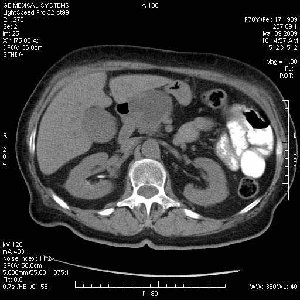

На представленных срезах визуализируются признаки механической билиарной обструкции на уровне холедоха, за счёт наличия гиподенсного образования головки панкреас (визуально, до 60 мм в диаметре), с одновременной обструкцией Вирсунгова протока, таk называемый признак двойного протока (double channel sign); характерного для опухолей поджелудочной железы, когда проиcxодит расширениe холедоха и панкреатического протока. Образовaние не распространяется на близлежащие SMV и SMA, т.е. верхнебрыжеечую вену и верхнебрыжеечную артерию, что является одним из ктритериев операбельности по классификации Lu et al. Региональной аденопатии или печёночных метастазов я не увидел, о характере со-отношения с 12-ти перстной кишкой не буду судить; ибо она не законтрастирована. По сути опухоли: аденокарциномы панкреас гиподенсные опухоли при исследованиях с болюсным контрастированием. Если опухоль имеет кистозную структуру, в диф. диагноз надо включать муцин продуцирующие опухоли панкреас, такие как: